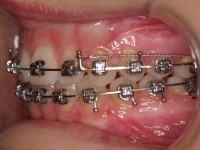

Clase II paciente 15 años

La paciente O.O. acude a nuestra consulta por:

– Canino 13 e incisivo lateral 42 en posición ectópica.

– Canino 23 incluido.

Con lo que decide realizarse un tratamiento de ortodoncia de duración de 24 meses con brackets damon Q.

CASO COMPLETO: